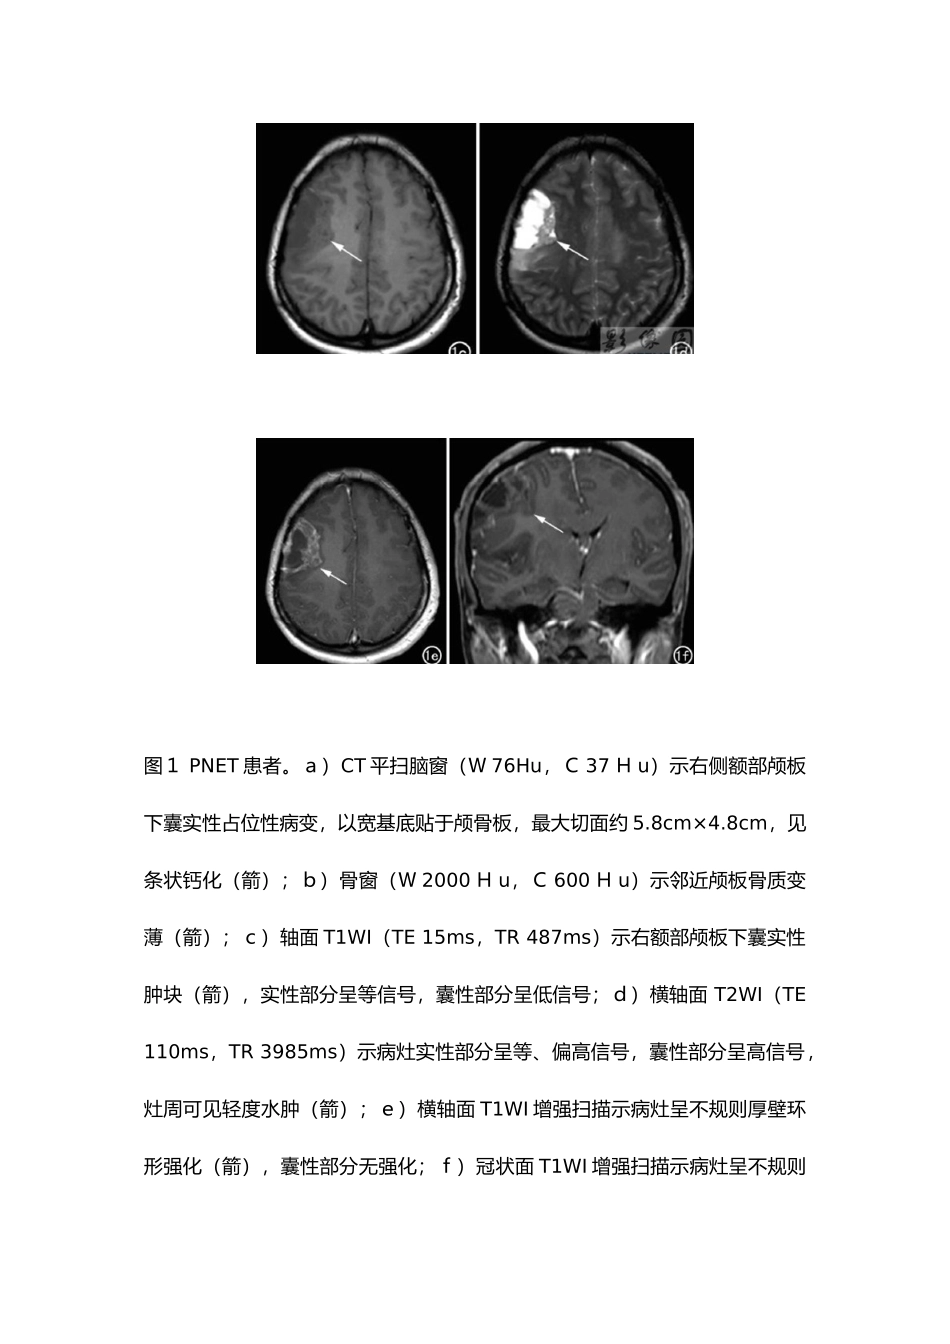

案例一 中枢神经系统原始神经外胚层肿瘤(CNSPET)-放射学实践系列病例[临床病史]:患者,女,37 岁,外伤后行头颅 CT 检查发现右侧额叶病变,为进一步检查收入我院,既往史无特别。查体:神志清,查体合作,对答切题。实验室检查无异常。[影像图片]图1 PNET 患者。a)CT 平扫脑窗(W 76Hu,C 37 H u)示右侧额部颅板下囊实性占位性病变,以宽基底贴于颅骨板,最大切面约 5.8cm×4.8cm,见条状钙化(箭);b)骨窗(W 2000 H u,C 600 H u)示邻近颅板骨质变薄(箭);c)轴面 T1WI(TE 15ms,TR 487ms)示右额部颅板下囊实性肿块(箭),实性部分呈等信号,囊性部分呈低信号;d)横轴面 T2WI(TE 110ms,TR 3985ms)示病灶实性部分呈等、偏高信号,囊性部分呈高信号,灶周可见轻度水肿(箭);e)横轴面 T1WI 增强扫描示病灶呈不规则厚壁环形强化(箭),囊性部分无强化;f)冠状面 T1WI 增强扫描示病灶呈不规则环形强化,囊性部分无强化(箭);g)病理图示肿瘤由致密的小圆细胞构成,细胞核深染,核仁不明显,细胞密集。[影像表现]:CT 检查:右侧额部颅板下囊实性占位性病变,最大切面约5.8cmX4.8cm,见条状钙化,病灶以宽基底贴于颅骨板并邻近颅板骨质变薄侧脑室受压,中线结构轻度左移(图 a-b)。MRI 检查:右额部颅板下囊实性肿块,实性部分呈等 T1、长 T2 信号,灶周轻度水肿,增强扫描呈不规则厚壁环形强化(图 c~f)。[ 手 术 所 见 ] : 右 额 下 回 后 方 一 实 性 肿 物 , 其 基 底 为 脑 表 面 , 大 小 约5cmX5cm,质软,色暗红,血供丰富,无包膜,见肿瘤突出脑皮层表面并向四周硬膜下腔延伸,肿瘤侵入脑达 3cm,与正常脑组织分界不清。[病理结果]:考虑为中枢神经系统原始神经外胚层肿瘤(PNET)(图1g)。[讨论]:原始神经外胚层肿瘤(PNET)是一类由原始神经上皮细胞衍化而来的高度恶性肿瘤,侵袭性强、预后差。发生在幕上的 PNET 极为少见,仅占整个颅脑肿瘤的 0.1%左右,约 85%的患者为儿童,成人发病者更为罕见 。2024 年 WHO 将中枢神经系统胚胎性肿瘤中的幕上原始神经外胚层肿瘤(SPNET)以与位于脑干、脊髓的类似肿瘤归于一类,并改称为中枢神经系统原始神经外胚层肿瘤。 病理上肿瘤实质由类似胚胎神经管原始未分化细胞构成,细胞密度高,胞外水含量低,核分裂易见,Homer Wright 假菊形团块样结构为其特征性表现,可伴有出血...